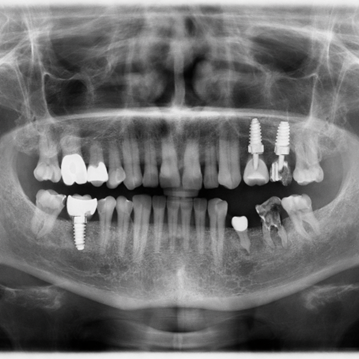

Digital X-rays

Provide a quick overview of your jawbone and existing dental condition

3D CBCT scans

1. Consultation & Scan – Your dentist evaluates your jawbone using X-rays or 3D scans to determine the need for grafting and plan the procedure.